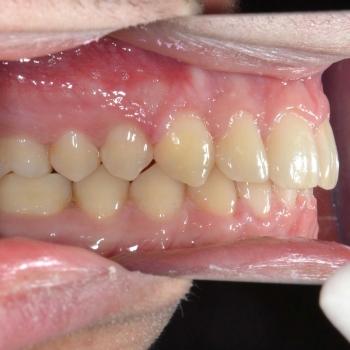

Ádám kitartásának köszönhetően a kezelés végére minden maradó fog a helyére került és egy esztétikailag és funkcionálisan is tökéletes harapást kaptunk.

A kezelés teljes időtartama: 3 év